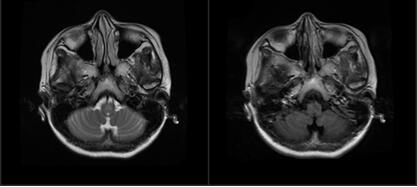

又过去了一个月,陈颖的症状不仅没有好转,而且病情还加重了,整个头部胀痛感,伴左侧脸面、肢体麻木感。至当地医院就诊,MR提示延髓及颈髓病变,按病毒性脑炎治疗后,症状没有明显好转。由于同乡人曾在广东三九脑科医院神经内一科治愈后出院,在听了别人的推荐后,家里人带着陈颖来到我院。

抵达我院后,匡祖颖主治医生考虑患者有明显消化道症状,外院诊查资料提示延髓及颈髓病变,初步诊断为中枢神经系统脱髓鞘性脑病,下一步完善检查明确病因。

考虑患者有典型的视神经脊髓炎的临床症状与影像表现,且特异性的免疫标志物AQP-4(+),最终明确诊断为视神经脊髓炎。

在NMOSD六组核心临床症候中,视神经炎、急性脊髓炎、最后区综合征最具有代表性。当抗体攻击第四脑室的延髓背侧等与呕吐反射中枢相关的区域,就会引起最后区症状,患者表现顽固性呃逆或恶心呕吐,这可以是疾病的前驱或唯一症状,需要引起临床医生的注意。

由于以最后区综合征起病的NMOSD患者早期消化道症状明显,多就诊于消化科或内科,易被延误诊治,加重患者残疾程度,增加患者复发几率。所以,当临床上遇到不明原因的顽固性呃逆、恶心、呕吐的患者,需要警惕NMOSD可能。建议对该类患者及时完善血清AQP4抗体检查和头颅MRI检查,避免误诊。